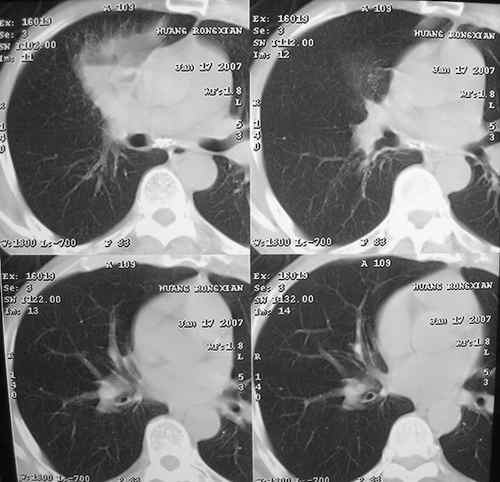

以下是引用dyqct在2007-1-18 22:22:00的发言:[br]右肺上叶前段见环形空洞样影,并见高位液平,内壁较光整,壁薄。纵隔未见肿大淋巴结,可见散在钙化灶。[br]考虑:1,肺脓肿;[br] 2,建议治疗后复查除外周围型肺癌。

以下是引用jiangjing在2007-1-18 23:45:00的发言:[br]右肺上叶前段见环形空洞样影,并见液平,周围可见片状模糊影,右肺上叶前段支气管通畅,纵隔未见肿大淋巴结,可见散在钙化灶,考虑肺部感染 肺脓肿可能。建议结合临床及抗炎治疗半月复查。其他待排